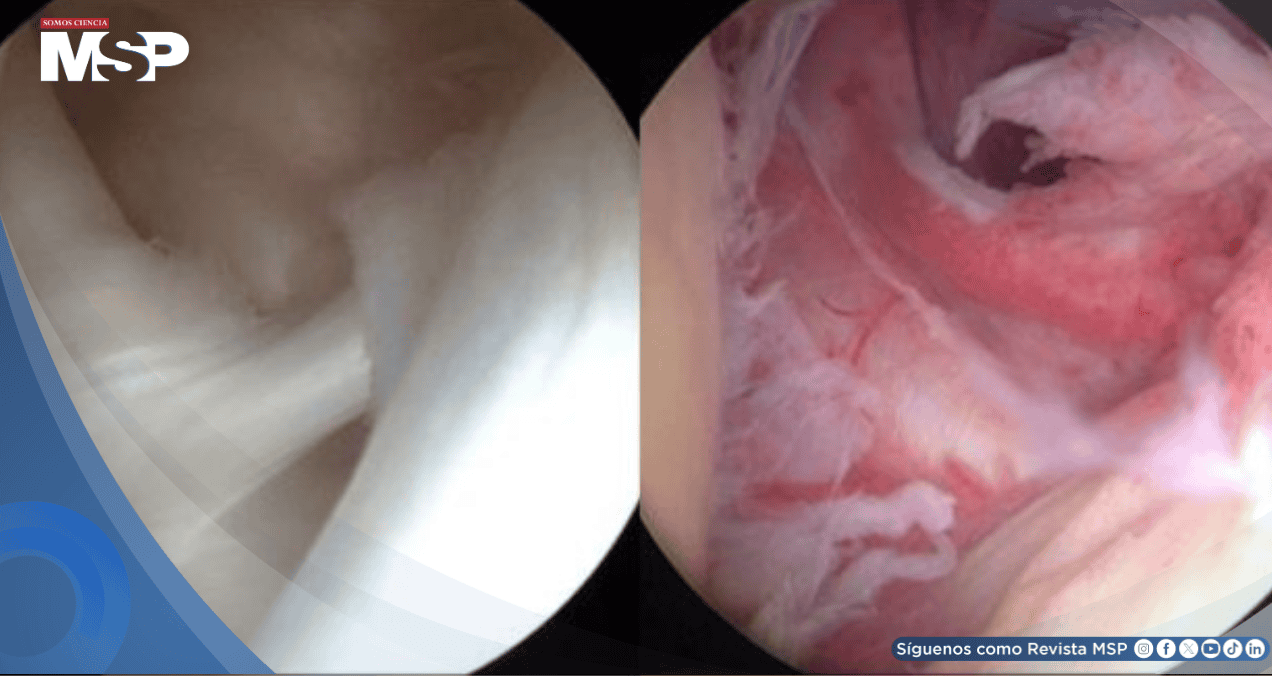

En el hombro congelado, la cápsula del hombro se vuelve más gruesa y rígida, y se forman bandas duras de tejido conocidas como adherencias. Además, en muchos casos, disminuye la cantidad de líquido sinovial en la articulación.

2. Tratamiento quirúrgico: En casos más severos, se puede considerar la cirugía, que incluye manipulación bajo anestesia y artroscopía del hombro. Estos procedimientos ayudan a liberar la cápsula rígida y aumentar el rango de movimiento. La recuperación puede tardar de 6 semanas a 3 meses, con una necesidad crucial de terapia física postoperatoria.